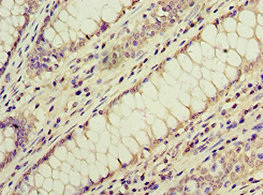

ACVR1C Antibody; CSB-PA854112ESR1HU